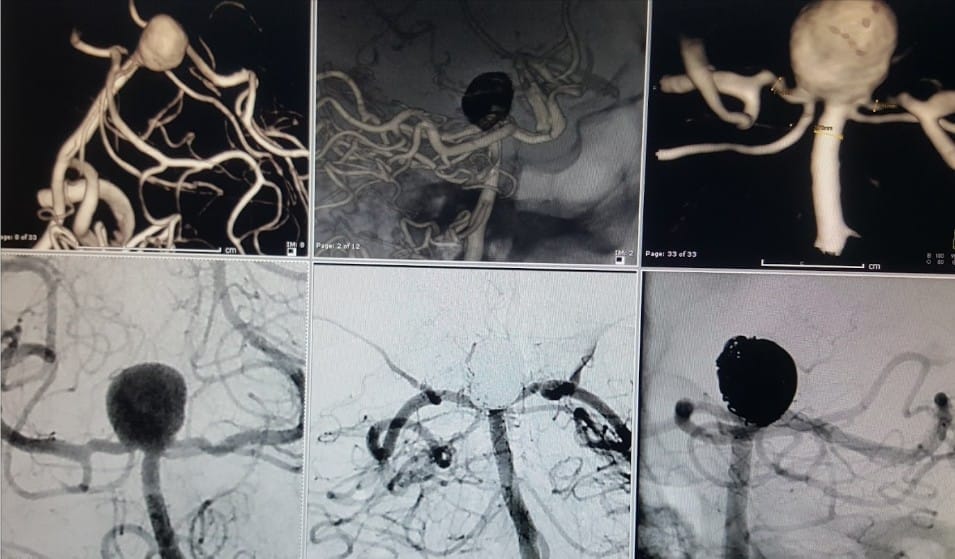

Damarların çatallanma noktasından çıkan anevrizmalarda; dalları korumak için stentlerden faydalanılır. Hem damarlar korunur hem de anevrizma koille daha iyi doldurulur. Bu işlem kapalı yöntemle yapıldı ve hastamız 2.gün taburcu oldu.